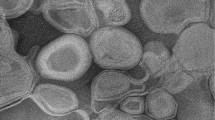

Figure 2 provides the cryo-TEM image of YSA-L-DOX. The TEM image clearly illustrates that our targeted liposome vesicles are round, membrane shapes structures. TEM also confirmed that our liposomal DOX samples consist of a mixture of multilamellar (two bilayers) and unilamellar liposomes and the majority had diameters of less than 100 nm. Additionally, the image shows that the vesicles tend to aggregate and form larger vesicles.